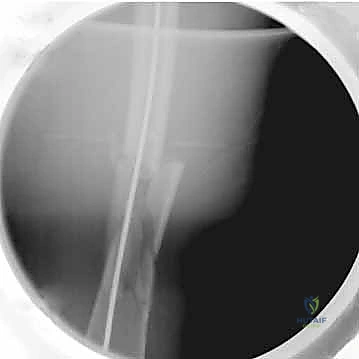

5. إدخال المسمار النخاعي

يتم إدخال المسمار المعدني بعناية فائقة فوق السلك التوجيهي حتى يعبر منطقة الكسر ويستقر في الجزء السفلي من الفخذ.

يتم إدخال مسامير قفل عبر المسمار النخاعي من الأعلى (بالقرب من الورك) ومن الأسفل (بالقرب من الركبة) باستخدام أجهزة توجيه دقيقة لضمان عدم تحرك الكسر.